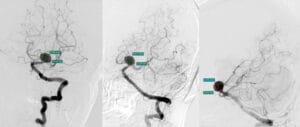

Embolización de varices pélvicas

El Dr. Andrés Guirola realiza embolización de varices pélvicas mediante cateterización de la vena gonadal.